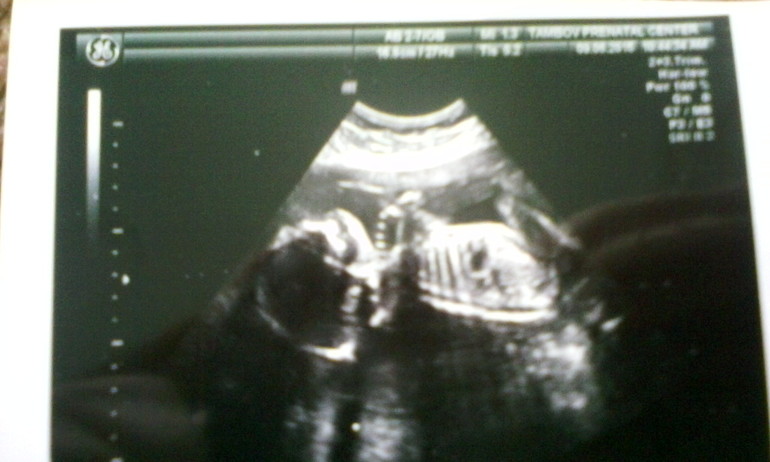

Итак, мы были на узи в 4Д. Нам так круто все объяснили, все показали. Наша малышка весит 2200 г. Никак не хотела она фотографироваться, упиралась в стенку матки носиком, но потом все таки мы ее подловили и удалось сделать фоточку.

По узи получился срок 33+4 дн - как по моим подсчетам.